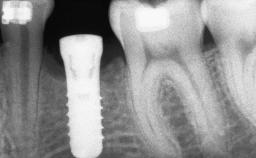

A 46-year-old woman was referred for treatment whose main complaints were mobility of her fixed partial dentures (right maxilla and left mandible) and periodontal bleeding during function. She also reported having taken systemic antibiotics to treat recurrent swelling in the area of the upper left molars. The patient had not seen a dentist for at least 2 years. She did not smoke and had no history of major systemic disease other than two minor orthopedic procedures some years back. The first-visit examination revealed poor plaque control, tooth mobility, periodontal disease, and a residual dentition widely associated with deep periodontal pockets.

Bone Augmentation Horizontal|Staged|Vertical

Bone Volume Deficient vertically or deficient vertically AND horizontally